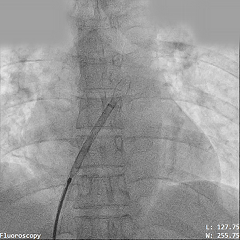

导丝过隔

PannaWire多功能导丝“让过隔更简单”

选择1224S规格导丝过缺损,PannaWire多功能导丝配合MPA导管通过ASD送至左心房

导丝通过ASD固定在肺静脉处

梭形头端可固定在肺静脉处,稳定防脱,建立稳定输送轨道